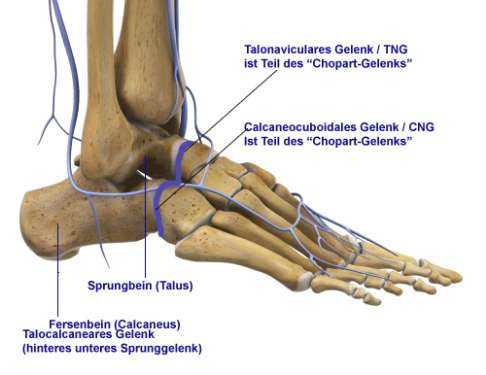

Setzt sich zusammen aus dem Gelenk zwischen Sprungbein und Kahnbein (talonaviculares Gelenk) und dem Gelenk zwischen Fersenbein und Würfelbein (calcaneocuboidales Gelenk).

Bei einer Triple-Arthrodese werden alle drei Anteile des unteren Sprunggelenks versteift, also alle Fußgelenke, die mit dem Sprungbein verbunden sind. Dazu zählen das zwischen dem Sprungbein und dem Fersenbein liegende talocalcaneare Gelenk (TCG oder Subtalargelenk) und die beiden vor dem Sprungbein liegenden Gelenke: das Sprungbein-Kahnbein-Gelenk (talonaviculares Gelenk, TNG) und das Fersenbein-Würfelbein-Gelenk (calcaneocuboidales Gelenk, CCG), welche gemeinsam das sog. Chopart-Gelenk bilden.

Das calcaneocuboidale Gelenk als Teil der Chopart-Gelenklinie

Die Rolle des Chopart-Gelenks

Die vorderen Anteile des unteren Sprunggelenks (TNG und CCG) bezeichnet man auch als Chopart-Gelenk. Bei einer möglichen Versteifung des oberen Sprunggelenks übernimmt das aus den beiden vorderen Anteilen des unteren Sprunggelenks zusammengesetzte Chopart-Gelenk die gesamte Restbeweglichkeit des Sprunggelenks, also Heben und Senken des Fußes. Das Chopart-Gelenk wird auch als Articulatio tarsi transversa – als vertikal bewegliches Fußgelenk vor dem Sprungbein bezeichnet. Es verläuft an der Fußwurzel quer zur Längsachse des Fußes und erbringt nach einer Versteifung des oberen Sprunggelenks die gesamte noch verfügbare Beweglichkeit des Fußes in vertikaler Richtung. Dabei unterstützt es dann auch in erheblichem Ausmaß die Abrollbewegung des Fußes.

Das calcaneocuboidale Gelenk (CCG) zwischen Fersenbein und Würfelbein trägt am wenigsten zur Gesamtbeweglichkeit des unteren Sprunggelenks bei. Es ist selten alleine von einer Arthrose des unteren Sprunggelenks betroffen, sondern fast immer als Folge von Störungen in den anderen Teilen des unteren Sprunggelenks. Vor allem als Teil des Chopart-Gelenks ist es von Bedeutung.